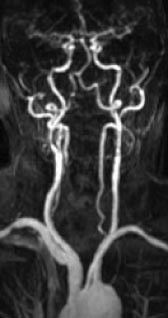

Intrakraniale kar

Kontrastforsterket MRA har foreløpig for dårlig romoppløsning for intrakranialt bruk. Den MRA-metoden som er best egnet for fremstilling av intrakraniale arterier, er 3D-innstrømnings-MRA (fig 3). Ved hjelp av denne metoden kan man påvise stenoser og okklusjoner av de større arteriene. Både MRA og CT-angiografi kan fremstille intrakraniale aneurismer med diameter på 5 mm eller mer med stor nøyaktighet (10, 11), for mindre aneurismer synes CT-angiografi å være noe bedre enn MRA. De ikke-invasive metodene kan bidra ved planlegging av behandling av aneurismer (kirurgisk eller radiologisk intervensjon), men metodene har ennå ikke kunnet erstatte kateterangiografi (12). Ved intrakraniale arteriovenøse malformasjoner er MR-snittbilder den metoden som best viser den anatomiske lokaliseringen av nidus (13). MRA kan gi en bedre anatomisk oversikt over hele malformasjonen, særlig om man benytter fasekontrast-MRA, som gir best fremstilling av både arterie- og venesiden. Både kirurgi og endovaskulær embolisering krever imidlertid en detaljfremstilling som bare kan gis av kateterangiografi.